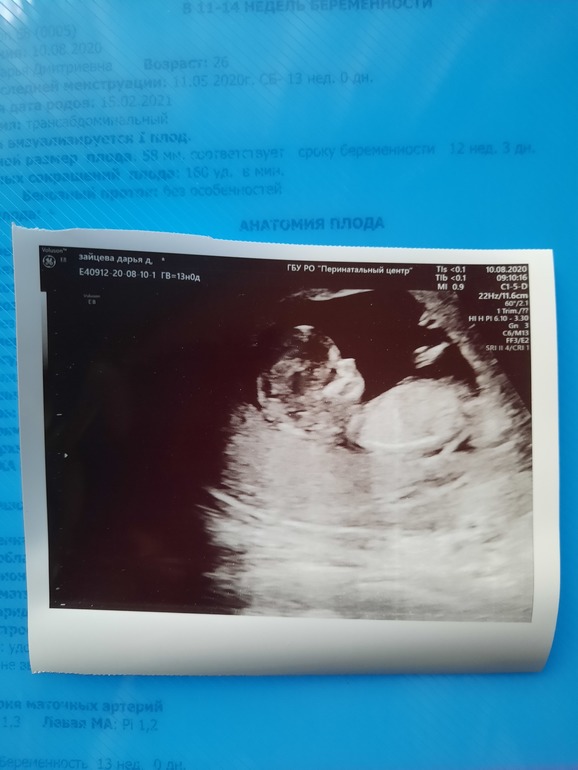

ПДР по УЗИ выставили на 20.02.2021 :)

Божечки, девочки! Это непередаваемое ощущение видеть свое 6-ти сантиметровое чудо, бултыхающееся в тебе))) Ножки задрал, ручками мне махал! Передавал привет, видимо 🤣 Я аж прослезилась, хотя не думала изначально плакать😅

УЗИ делала очень добрая женщина, которая на экране выводила мне пупсика. Ничего не рассказывала, но в конце сказала, что все в норме. Сердечко дали послушать и эти "ту-дум-дум" прям дух захватывают))